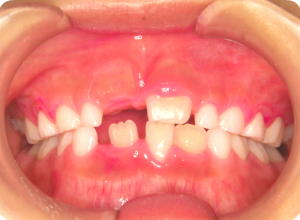

③それぞれのお口の大きさに合わせたトレーを使い、フッ素を塗布していきます。